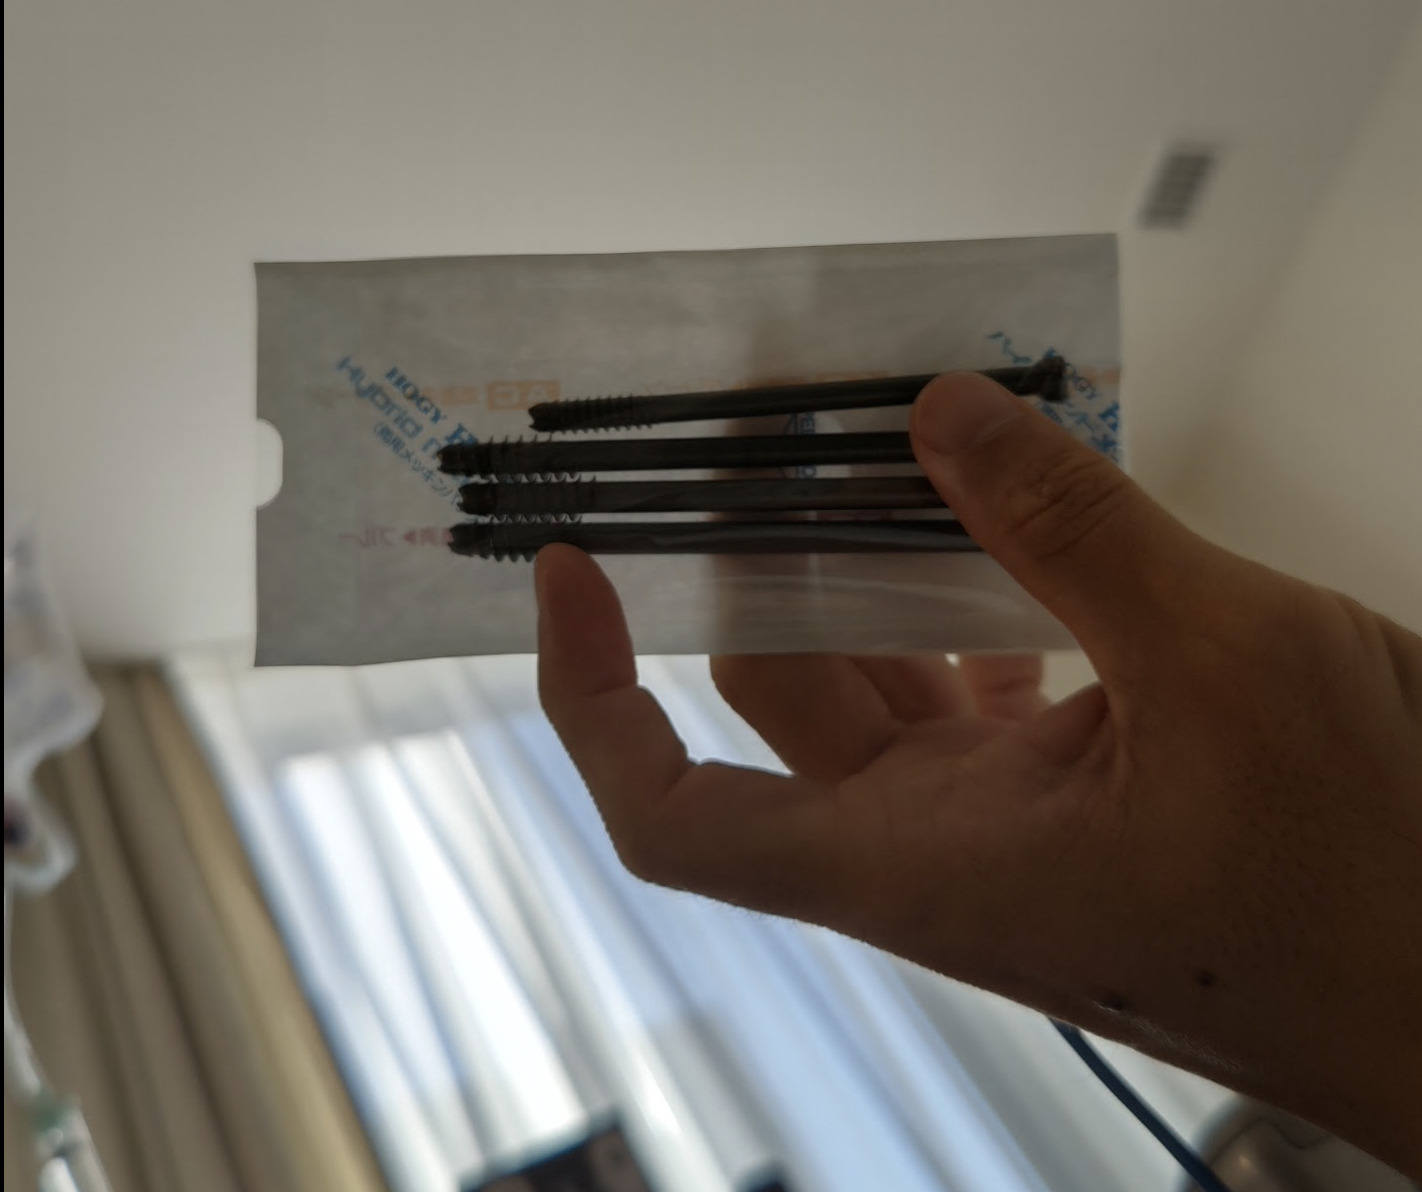

これが抜いたピン。

レントゲンでみて、大きさはわかっていましたが、いざ目にすると驚きました。

ピンを入れるときも、ピンを抜くときも、1cmほど切り、筋肉をかき分けて(ちょっと切るらしい)、こういったピンを入れるのはすごい技術だなと。

本当に感謝です。

全身麻酔から目覚めたとき、聞いたのは、時刻とピンのことでした。

目覚めたときには「いよいよか……」と思っていたのですが、「終わりましたよ」と言われて、「えっ」という感じでしたけど。

先生がピンを見せ、手に持たせてくれました。

4本あったので、「4本とも取れたんだ」と。